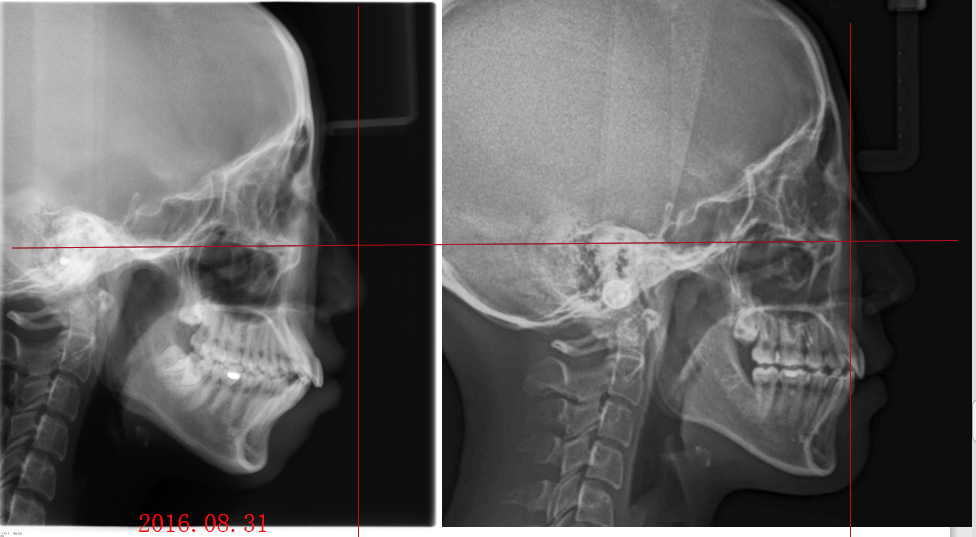

_PRE-TXNorm FMIA°47°55.0SNA°77.7°83.0SNB°70.2°80.0ANB°7.5°3.0FMA° 29.826PFH/AFH70.5°70Z Angle°50.3°77U1-FH113.0110.0IMPA°103.297.0U Lip to s’ line6.3 mm5.0L Lip to s’ line3.9 mm3.0OP-FH1215

头侧位片:

▲下颌后缩,骨性Ⅱ类

▲高角,颏部发育不足

▲上下前牙唇倾

Post-TXPRE-TXPost-TXNormFMIA°47°57.555.0SNA°77.7°76.883.0SNB°70.2°73.780.0ANB°7.5°3.13.0FMA° 29.828.026PFH/AFH70.5°65.970Z Angle°50.3°64.477U1-FH113.0103.7110.0 IMPA°103.291.197.0U Lip tos’ line6.3 mm3.25.0L Lip to s’ line3.9 mm1.03.0OP-FH1212.615